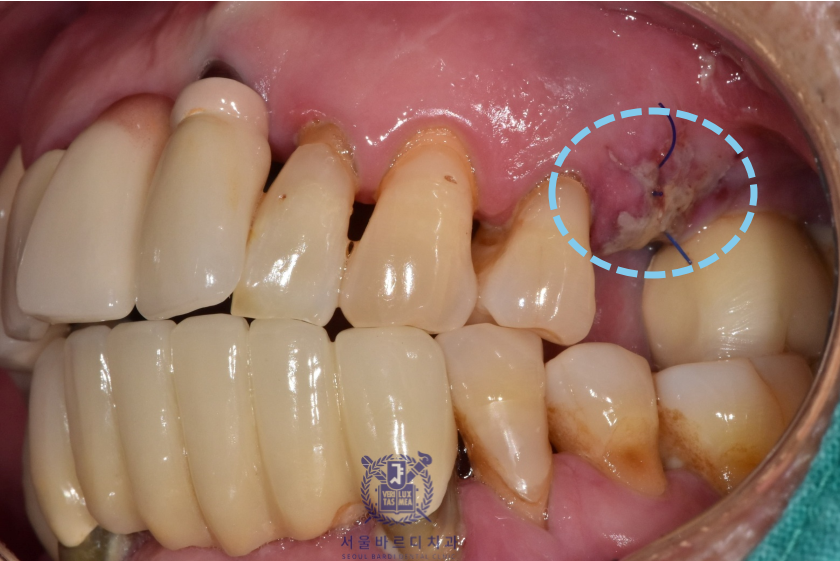

왼쪽 위 역시 가장 이상적인 위치에 성공적으로 임플란트를 식립하였습니다.

다행히 수술 후 지혈도 잘 되시고 회복하는 과정에도

환자분이 지시에 잘 따라주셔서 잇몸도 예쁘게 아물었습니다.

아래 앞니는 6개의 치아를 안정적으로 유지할 수 있는

견고한 4개의 뿌리를 식립하였고

왼쪽 위는 큰어금니 다음으로 중요한 역할을 수행할 작은

어금니에 맞는 사이즈로 식립하였습니다.